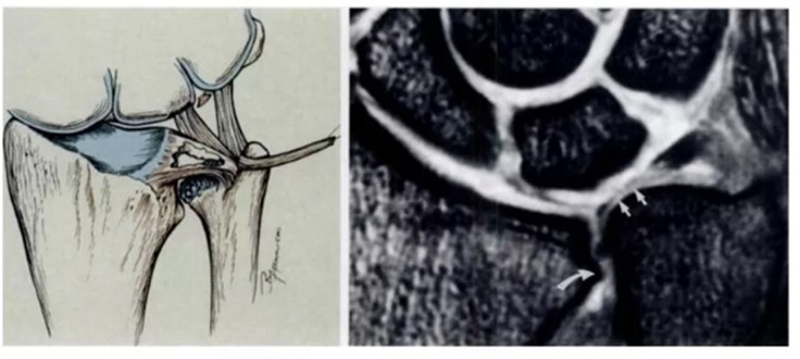

ⅠB,TFCC尺侧撕裂;TFC尺侧附着处信号增高

ⅠC,尺三角韧带撕裂